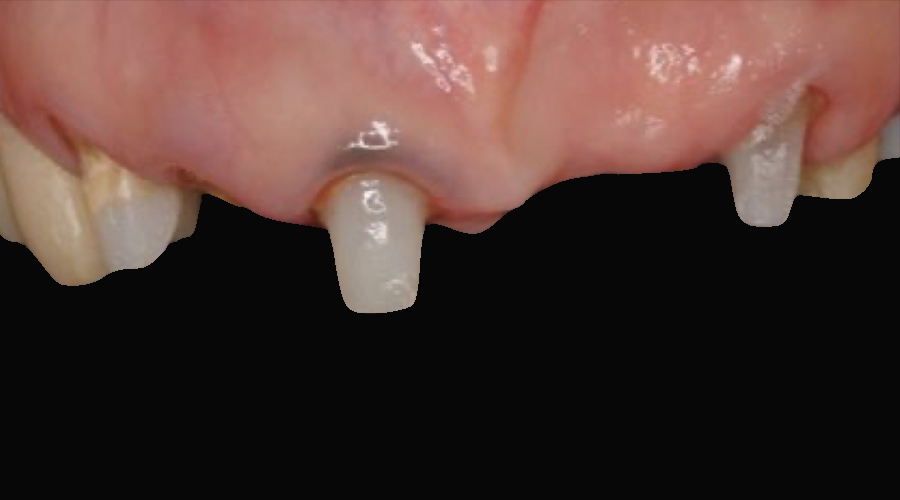

- 治療内容

- 欠損部位に対して、人工歯根を埋入し上部構造として補綴物をかぶせる治療です

- 治療に伴うリスク

- 治療後の口腔管理が不適切な場合、埋入したインプラント周囲に感染・炎症を起こし、脱落する可能性がございます。